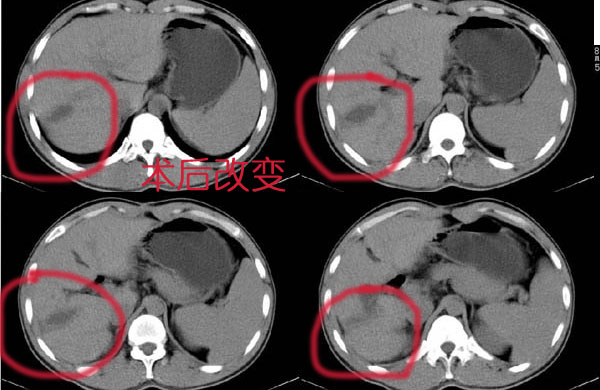

支持肝癌术后改变。

支持肝癌术后改变.

术后改变